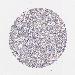

OVARIAN CANCER - Protein expressioni

A mouse-over function shows sample information and annotation data. Click on an image to view it in a full screen mode. Samples can be filtered based on level of antibody staining by selecting one or several of the following categories: high, medium, low and not detected. The assay and annotation is described here.

Note that samples used for immunohistochemistry by the Human Protein Atlas do not correspond to samples in the TCGA dataset.

Antibody stainingi

Antibody staining in the annotated cell types in the current human tissue is reported as not detected, low, medium, or high, based on conventional immunohistochemistry profiling in selected tissues. This score is based on the combination of the staining intensity and fraction of stained cells.

Each image is clickable and will lead to virtual microscopy that enables deeper exploration of all samples and also displays staining intensity scores, fraction scores and subcellular localization as well as patient and tissue information for each sample.

Antibody HPA003425

Antibody CAB002170

Cystadenocarcinoma, serous, NOS

Cystadenocarcinoma, mucinous, NOS

Carcinoma, endometroid